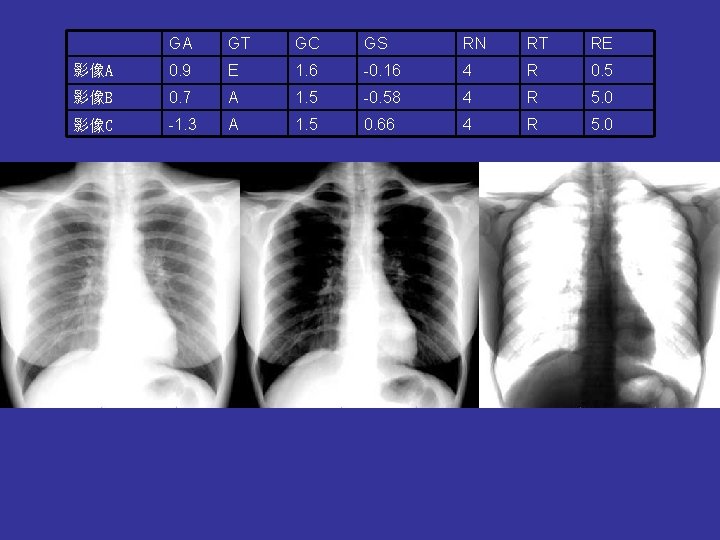

GA GT GC GS RN RT RE 影像A 0. 9 E 1. 6 -0. 16 4 R 0. 5 影像B 0. 7 A 1. 5 -0. 58 4 R 5. 0 影像C -1. 3 A 1. 5 0. 66 4 R 5. 0